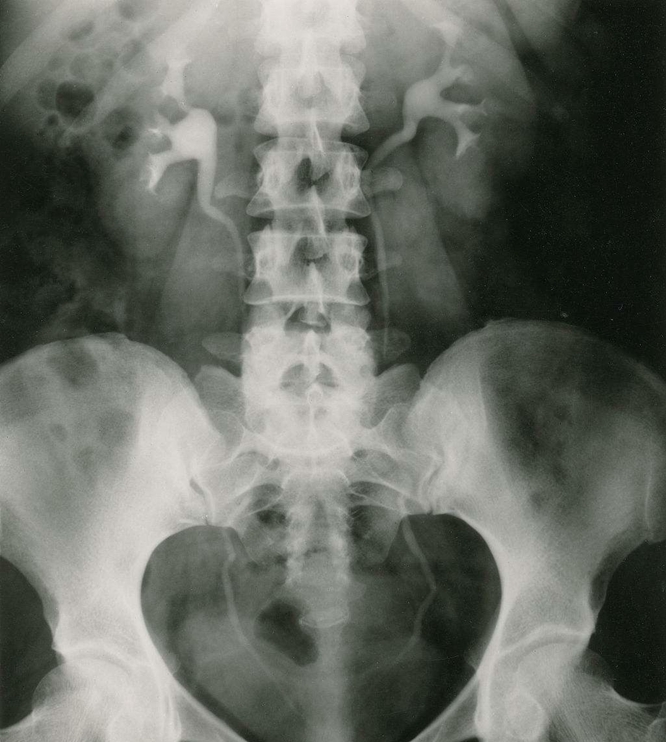

腹部平片:是泌尿系统常用的检查方法; 常规摄取仰卧前后位片。

泌尿系结石:约90%结石可由线平片显示,称为阳性结石;如尿酸盐结石难在平片上显示,称为阴性结石。肾结石可为单侧或双侧性,影像技术中表现为圆形、卵圆形、桑椹状、鹿角状或不定形密度增高阴影;密度可均匀、不均匀或分层状。大多发生在肾盏或肾盂部位,可单发或多发。输尿管结石多由肾结石移行而来,较小的米粒到黄豆大小,大的桑椹或枣核状大小;长轴与输尿管走行一致,常见于生理狭窄处。